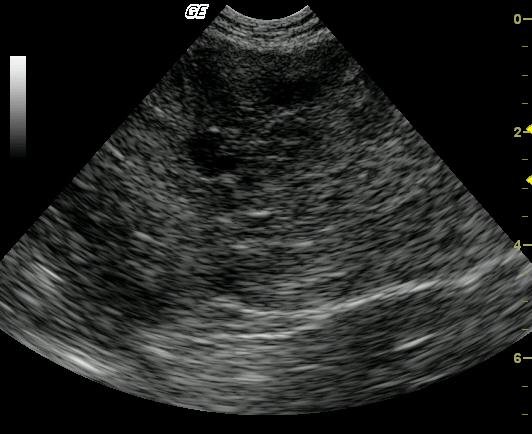

Long-axis view of the left lateral liver lobe reveals a large (5-cm), lobulated, complex, mixed echogenic, nodular mass arising from the left caudal liver. The mass is causing caudal displacement of the stomach, which was not in the view. The remaining left liver demonstrates a mildly echogenic parenchyma with evidence of portal venous congestion.